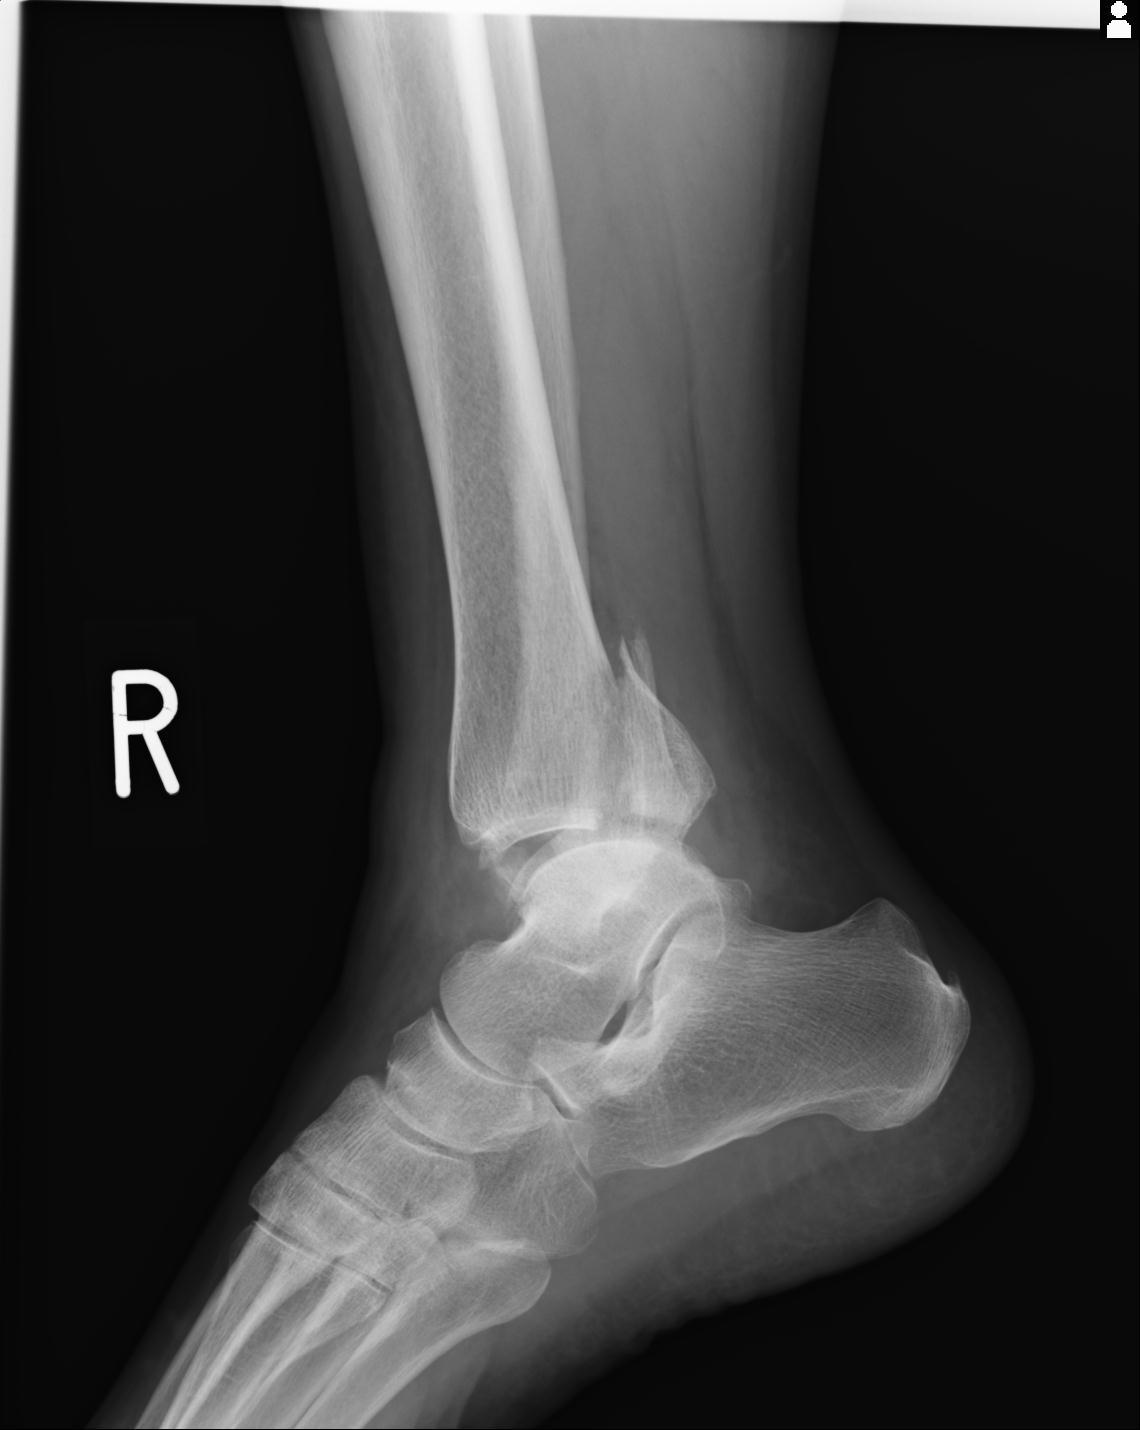

102755 1/4 2R 1/15 2R 右足関節 68歳女性 右三果脱臼骨折